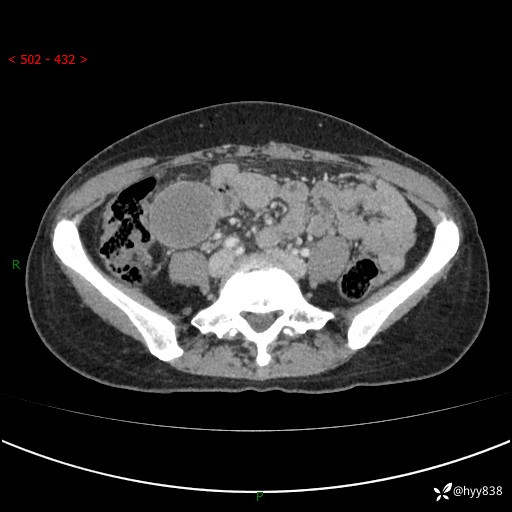

现病史:患者自诉于1周前无明显诱因出现剑突下间断性隐痛,尚可忍受,不向其它部位放射,无恶心呕吐、腹泻便秘等不适,于当地市第二人民医院就诊,行CT结果示:1.右中腹占位,间叶组织来源可能2.小肠梗阻3.盆腔积液4.腹腔积液5.副脾6.肝囊肿;于荆州二医行抗炎,抑酸,护胃,补液等对症支持治疗;患者病情好转,今为求进一步诊治,遂来我院门诊就诊,门诊以“腹腔肿瘤”收入院。 起病以来,患者精神、睡眠、饮食一般,大小便正常,近期体力体重无明显改变。

腹部CT增强(外院平扫)